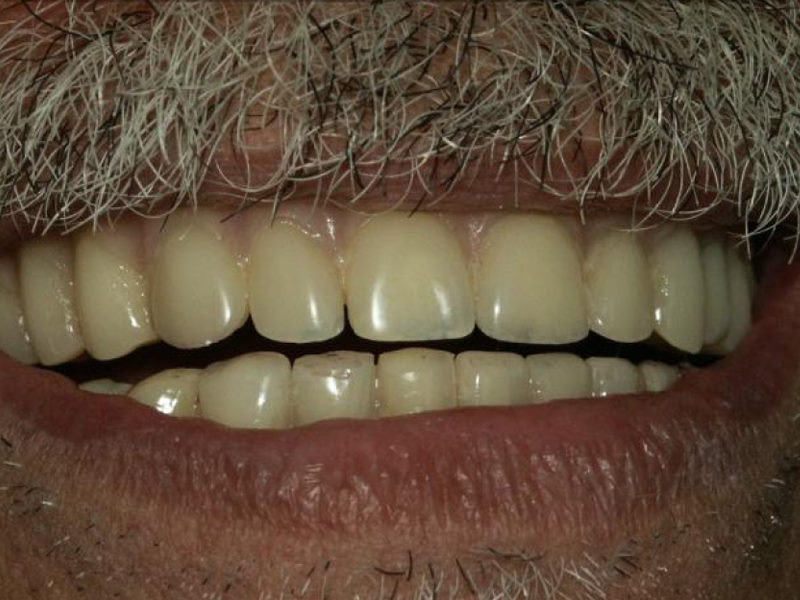

Foto en el cual al paciente se le colocaron cuatro implantes a nivel de maxilar superior

El mismo paciente en el cual se le colocaron cuatro Implantes inferiores, para elaborarle Prótesis Hibridas que van fijas